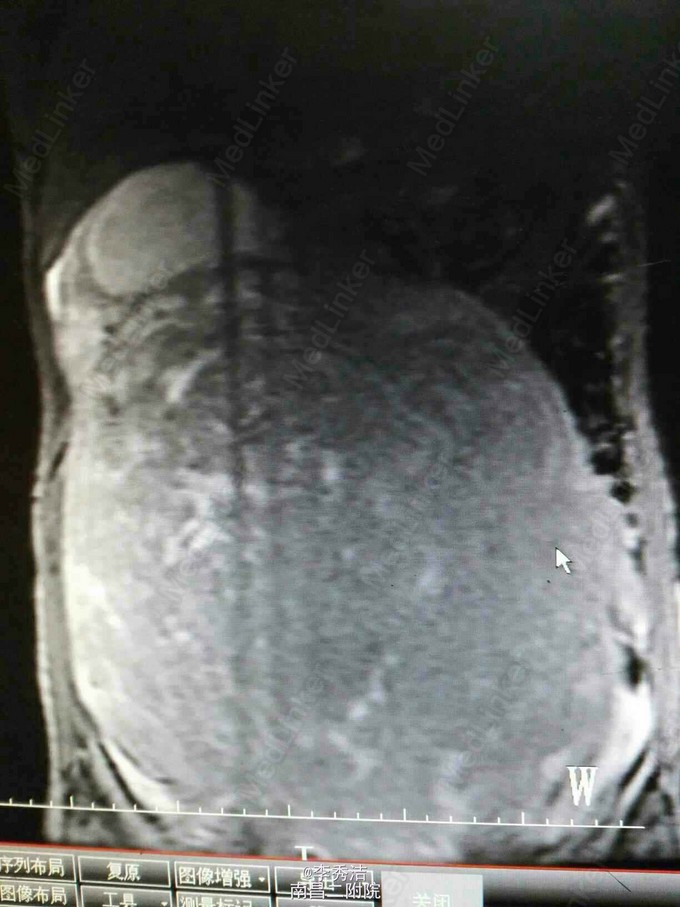

妇科检查:子宫孕9月大小,无压痛,活动。彩超示:子宫体积明显增大,内部呈蜂窝状考虑子宫肌瘤癌变,双侧附件区显示不清。腹部ct示:盆腹腔巨大肿块,子宫及双侧附件显示不清。

行剖腹探查术,术中见子宫血管显露,子宫底部触及一大小约35*30*12cm肌瘤样囊性包块,占据盆腹腔大部分,质软,表面光滑,充满手术野,包块与盆腔后壁肠系膜膜性粘连,右侧卵巢见一直径约5cm囊性包块,表面光滑。松解粘连后,行子宫肌瘤剔除术+右侧卵巢囊肿剔除术,剔除肌瘤16Kg。术中冰冻切片示:(子宫)初步考虑平滑肌瘤伴出血、变性。右侧卵巢良性囊性病变。诊断为1.子宫肌瘤变性,2.右侧卵巢囊肿。